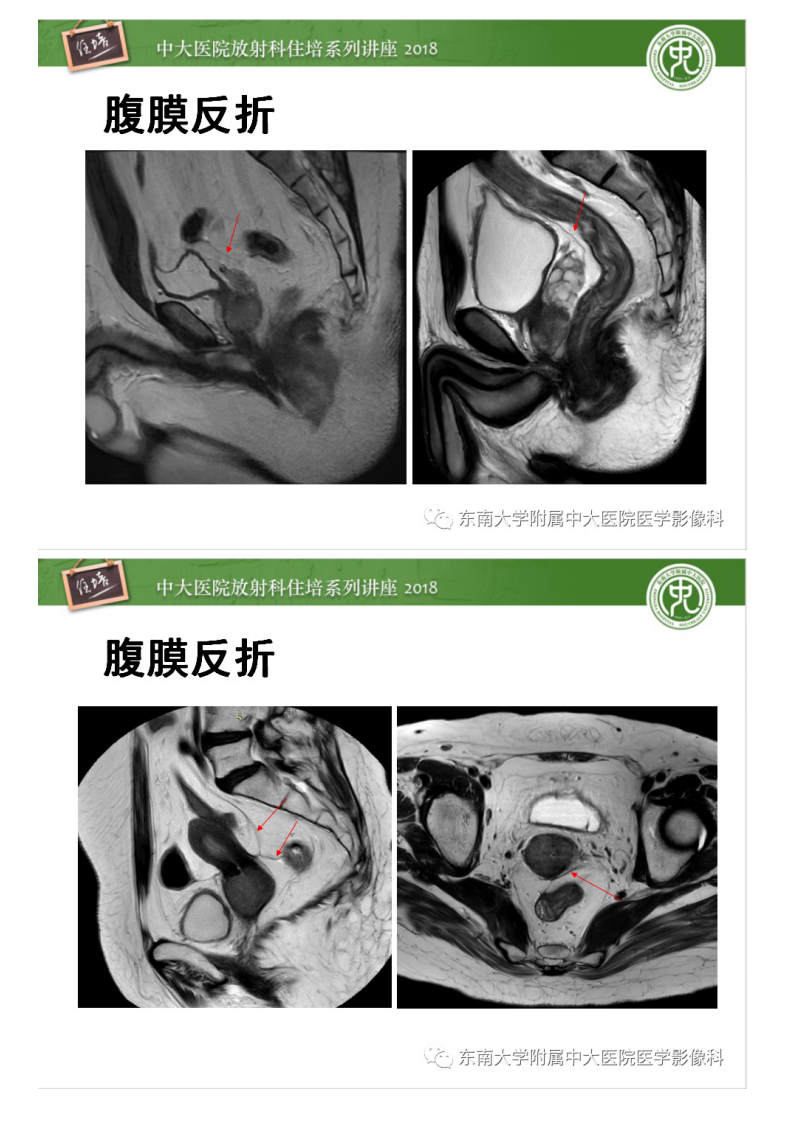

20200409_1【中大放射住培系列讲座】直肠癌MR分期及报告.pdf